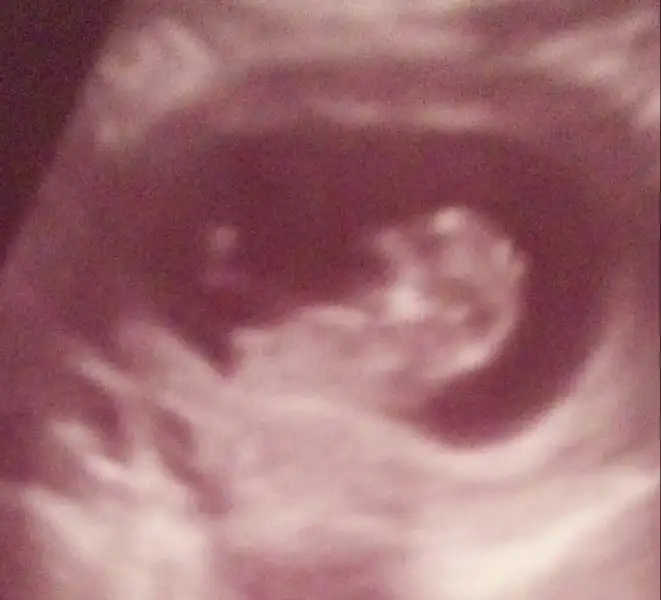

kizlar benim minnak ;) cinsiyyet tahmini olan var mi?@zenderu kalp atim 162 idi.140ustu kiz derler dogrumu acaba?

Eki Görüntüle 2054784 kizlar benim minnak :KK66: cinsiyyet tahmini olan var mi?@zenderu kalp atim 162 idi.140ustu kiz derler dogrumu acaba?

selamlar anneler :KK66: cinsiyete yavaştan geçiş yapılmış negüzel,ben de bu konuda müthiş meraklıyım hemen 16-17 haftalık olsa da öğrensem diyorum.12 haftada öğrenenler olmuş ama weryew weryew in başına gelen bana da olmuştu.bana da 12.haftada erkek dedi gittiğim doktor hatta birlikte bakıp benzettik,sonra 17.hafta da kesin kız dendi :KK66: oyüzden bence 17.hafta daha belirleyici sanırım cinsiyet konusunda. bu genital nub teorisi var hiç ona bakabildiniz mi? 8. - 12. haftalar arası alınan ultrason görüntülerine göre bakılıyor. eğer popo ucu sırt çizgisiyle paralel düz uzanıyorsa KIZ,popo ucunda sırt çizgisini açılayan bir çıkıntı varsa ERKEK deniyor.kızımın eski ultrason fotolarına baktım hakkaten onda tutuyor ama tesadüf müdür bilemem :KK53:ben bu hafta 9+3de kontrle gidicem görüntüyü bir yorumlamak istiyorum bakalım,heyecanım artsın :halay::anneadayı:

Kız bu canım bence nub göre